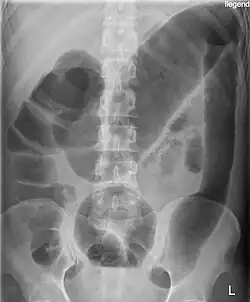

![]() Ostre rozdęcie okrężnicy u chorego z wrzodziejącym zapaleniem jelita grubego | |

Na podstawie obrazu klinicznego i przeglądowego zdjęcia RTG jamy brzusznej. Kryterium radiologicznym rozpoznania ostrego rozdęcia okrężnicy jest stwierdzenie średnicy okrężnicy poprzecznej w płaszczyźnie pośrodkowej większej niż 5,5 cm na zdjęciu przeglądowym jamy brzusznej[1].